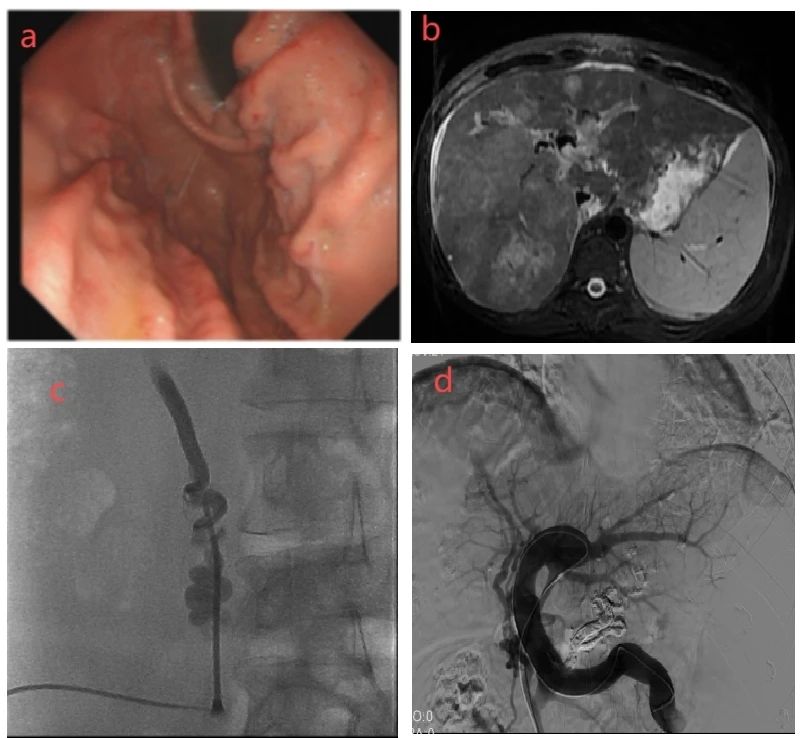

a.患者消化道出血前3个月胃镜提示食管胃底静脉曲张;

b.肝内多发病灶伴门静脉癌栓;

c.B超引导下经皮穿刺脐静脉成功;

d.经脐静脉入路导管进入胃底静脉栓塞成功